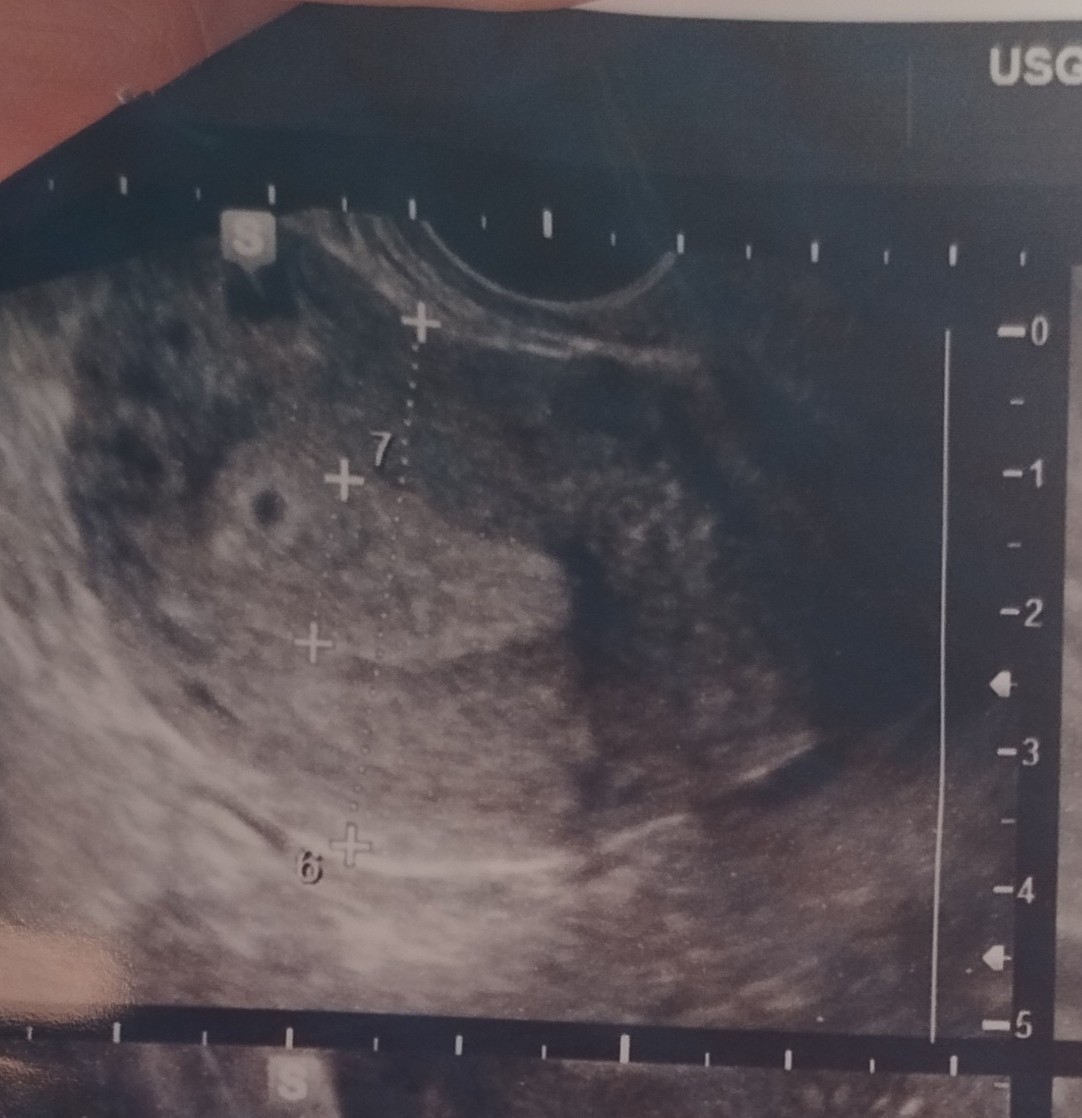

Oto mój pęcherzyk w 5+1, 9 dni później był zarodekJa dziś po pierwszej wizycie. 5+3. Widoczny był pusty pęcherzyk. Niby jest jeszcze czas ale to już mi złe myśli nasuwa ;(

Kolejna 3 lipca, już docelowo u mojego prowadzącego. W jakich tygodniach pojawiały się u Was pęcherzyki i zarodki?Na spokojnie, wszystko może zmieniać się z dnia na dzieńkiedy masz kolejna wizytę?

Ja mialam usg 6t3d i był zarodek z pulsującym układem krążenia (serduszko)Kolejna 3 lipca, już docelowo u mojego prowadzącego. W jakich tygodniach pojawiały się u Was pęcherzyki i zarodki?

To bardzo wcześnieJa dziś po pierwszej wizycie. 5+3. Widoczny był pusty pęcherzyk. Niby jest jeszcze czas ale to już mi złe myśli nasuwa ;(

Miałam wizytę w środę, też 5+3 i też tylko pęcherzykJa dziś po pierwszej wizycie. 5+3. Widoczny był pusty pęcherzyk. Niby jest jeszcze czas ale to już mi złe myśli nasuwa ;(